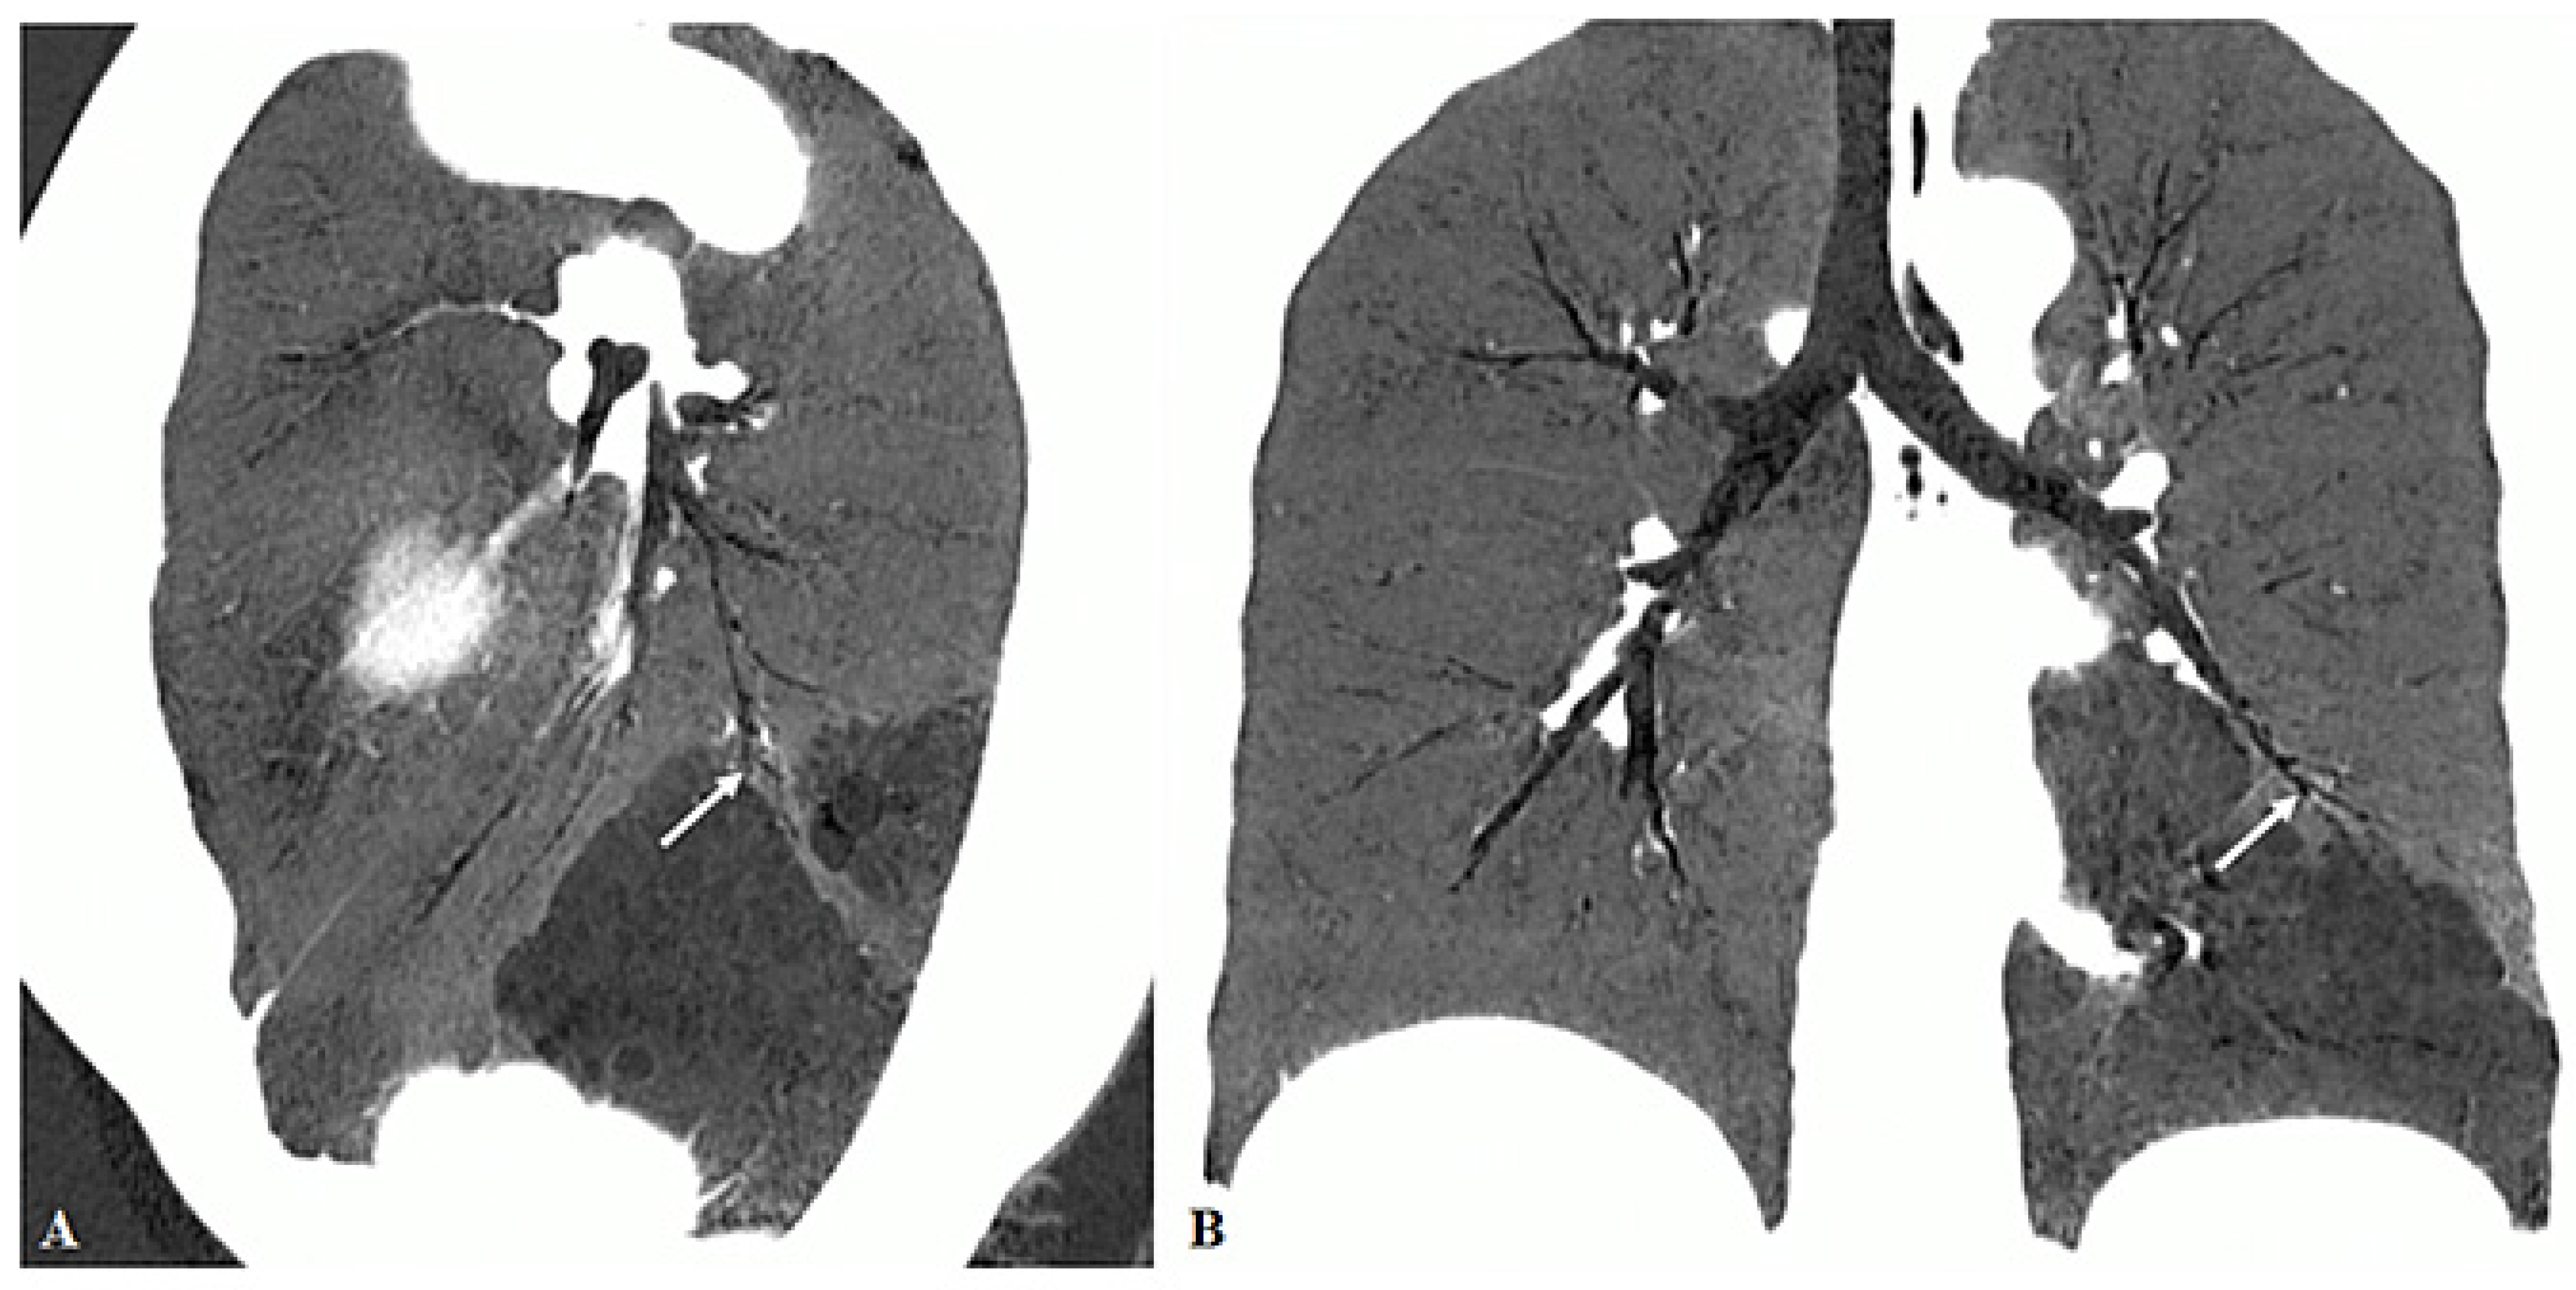

3.2. Imaging Appearances of CTPA